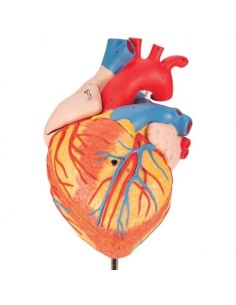

Dal cranio in 22 parti con incastri magnetici ai modelli di colonna vertebrale, da quelli di articolazioni a quelli di cuore, ogni pezzo della nostra collezione è progettato per un’immersione totale nello studio dell’anatomia umana. I nostri modelli, realizzati tramite scansioni di ossa vere, garantiscono un’esperienza tattile autentica e una fedeltà di peso quasi identica agli originali.